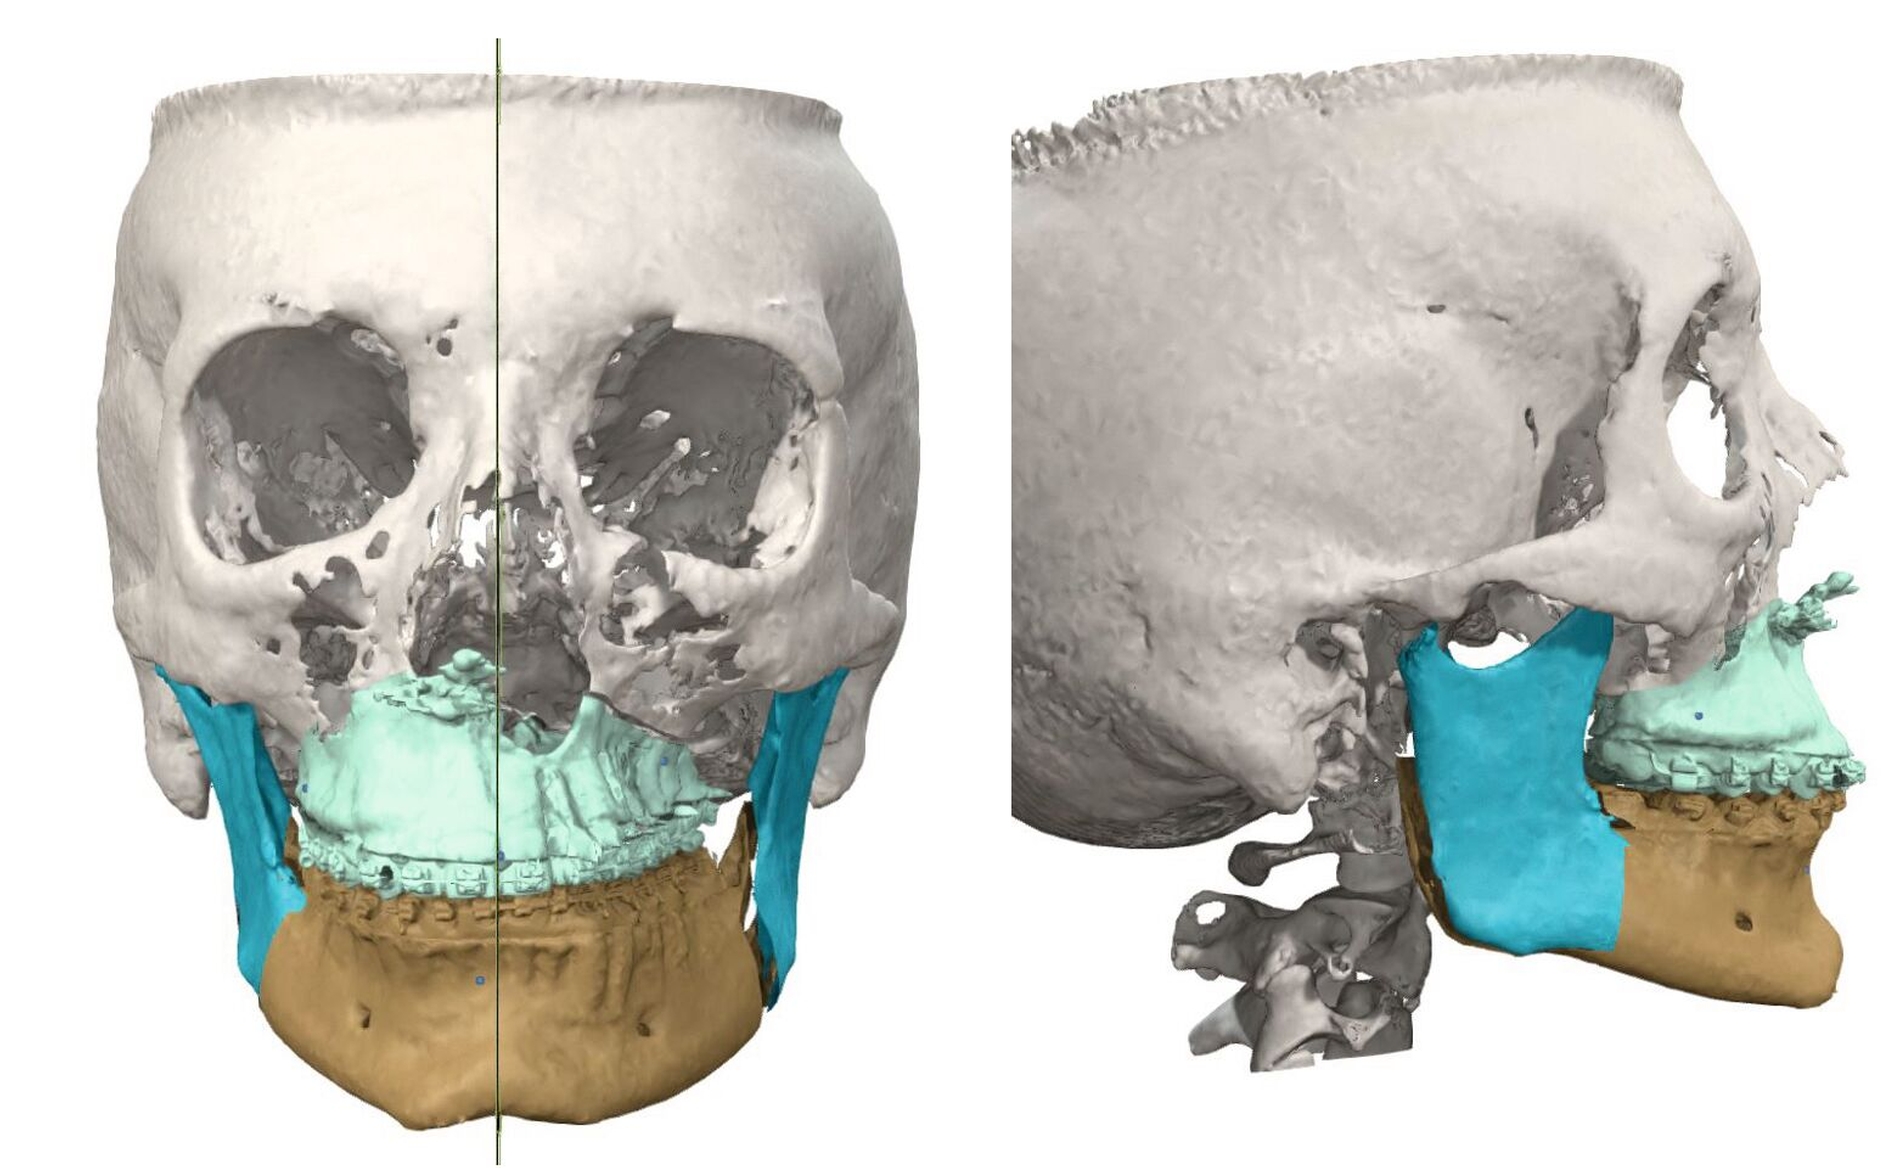

Gemeinsam mit den behandelnden Kieferorthopäden wurde aufgrund des abgeschlossenen Wachstums und der ausgeschöpften nicht-chirurgischen Maßnahmen die interdisziplinäre Indikation zur chirurgischen Korrektur der Dysgnathie gestellt. Anhand einer kephalometrischen Analyse trafen wir gemeinsam mit der Patientin die Entscheidung zur Durchführung einer bimaxillären Umstellungsosteotomie (Abbildung 3).

Der Eingriff konnte noch im selben Jahr komplikationslos in Intubationsnarkose durchgeführt werden. Nach digitaler Planung durch Matching der präoperativen DVT-Aufnahmen und der Intraoralscans wurden die Splinte für die Operation 3-D-gedruckt, nachdem die Zielokklusion festgelegt worden war. Der Oberkiefer wurde in der Le-Fort-I-Ebene osteotomiert und um 0,5 mm nach anterior und um 2,5 mm nach rechts verlagert. Durch die Kippung entstanden eine rechtsseitige dorsale Impaktierung um 1,5 mm und eine linksseitige Kaudalverlagerung um 1 mm. Der Unterkiefer wurde um 1 mm nach anterior verlagert, wobei es zu einer Schwenkung von 5 mm nach anterior links und um 2 mm nach posterior rechts kam (Abbildung 4).